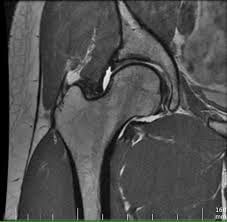

앉아 있을 때 느껴지는 불편감

고관절 통증은 걷거나 움직일 때뿐 아니라 가만히 앉아 있을 때도 나타날 수 있습니다.

• 오래 앉아 있으면 엉덩이 통증

• 의자에서 일어날 때 뻣뻣함

• 장시간 운전 후 통증

특히 장시간 앉아 있다가 처음 움직일 때 통증이 심해진다면 고관절 내부의 마찰이나 염증 가능성을 생각해볼 수 있습니다.